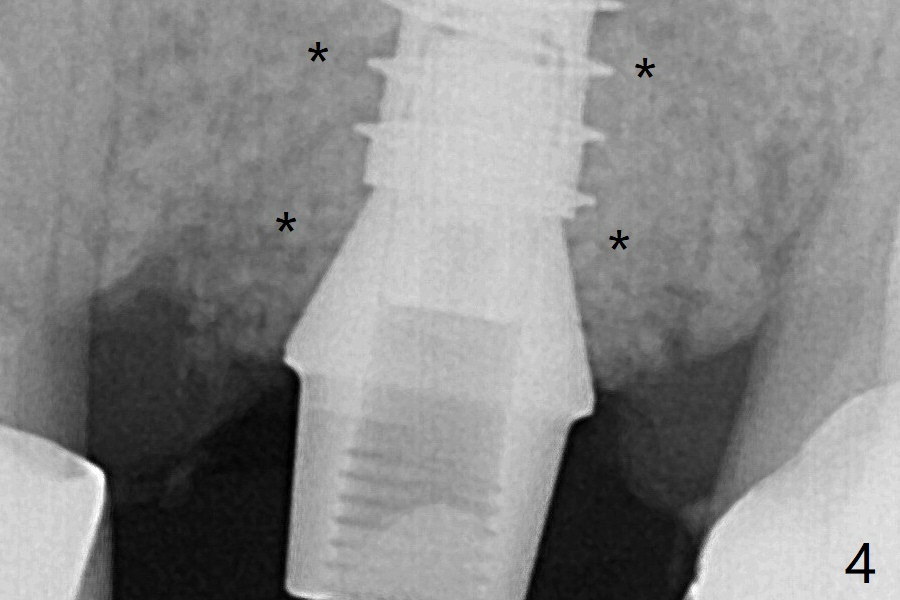

左上6腭侧退缩牙龈(图一:箭头)深部没有骨壁(图二:*),4.5x11毫米植体周围缺损(图三:*)由粘性骨粉(皮质骨,图四:*)填入。术后四个月骨粉形态接近原位骨(图八),但是腭侧软硬组织仍有缺损,炎症。